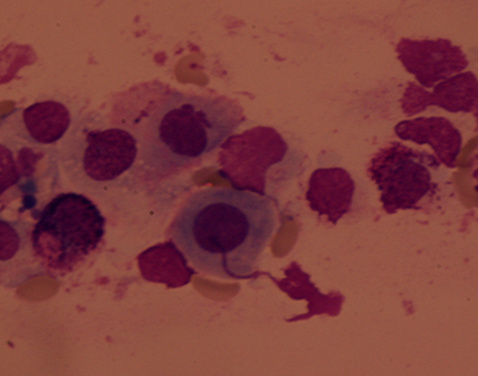

取得結膜刮片后將結膜刮片標本置于載玻片上,經固定后進行瑞氏(Wright)法染色,顯微鏡下觀察細胞學的變化,主要檢查的細胞為各種炎性細胞和結膜上皮細胞。對其進行脫落細胞學分類。過敏性結膜炎約半數患者可發現變性的上皮細胞及嗜酸性粒細胞。

嗜酸粒細胞。炎性腫脹的上皮細胞間及其附近見嗜酸粒細胞,核2~3葉,胞漿內密集粗大、規則一致的顆粒,呈亮紅色

上瞼結膜刮片見嗜堿性粒細胞

小淋巴細胞、活化的淋巴細胞